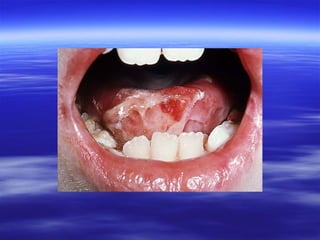

 Painless, soft, friable, and creamy plaques on the

mucosa.

 Can be easily wiped off, to expose an

erythematous mucosa or shallow ulceration.

 Their extent varies from isolated small flecks to

widespread confluent plaques.